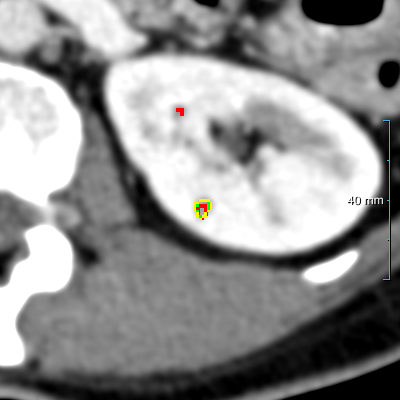

Figure 2: Example illustrating the different annotation formats. Each subfigure shows the same axial section, with overlays depicting the annotations: (a) shows the axial CT section. (b) shows the annotations in format 1: parenchyma and kidney abnormalities as a single structure (yellow overlay). (c) shows the annotations in format 2: parenchyma (yellow overlay) and kidney abnormalities (red overlay) as different structures. All images have a window center of 60 HU and a window width of 360 HU.

This study utilized two annotation formats, format 1 and format 2, to store the annotations. Format 1 considers the kidney parenchyma and kidney abnormalities as a single class (see Figure 2(b)) while format 2 separates them into two classes (see Figure 2(c)).